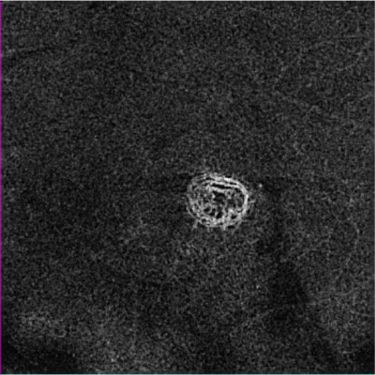

Zeiss Medical Technology (Dublin, CA) has received FDA clearance for its AngioPlex OCT angiography technology, which enables ophthalmologists to use optical coherence tomography (OCT) images to assess the blood vessels (vasculature) of the retina at a depth and clarity never available before. The technology delivers high-resolution, depth-resolved visualization of the separate layers of the retinal and choroidal vasculature without the need for an injected contrast dye, as is standard with fluorescein angiography (FA).

AngioPlex OCT angiography clearly visualizes blood flow by detecting motion of scattering particles, such as red blood cells, within sequential OCT B-scans performed repeatedly at the same location of the retina. Unlike other OCT angiography systems that require multiple OCT scans to generate one single OCT angiography image, the company's CIRRUS HD-OCT system with AngioPlex only requires a single additional OCT scan. The key to this is the real-time retinal tracking system, FastTrac, that actively eliminates eye motion to provide motion-artifact-free images of the perfused retina. Equally important, FastTrac enables follow-up OCT angiography images to be acquired at the same precise location to assess treatment efficacy and monitor disease progression.

AngioPlex is powered by Optical Micro Angiography (OMAG) algorithms to provide ultra-clear vascular images. OMAG is an image processing technique that takes full advantage of not only amplitude, but also phase OCT signal data to deliver the highest-quality OCT angiography images.